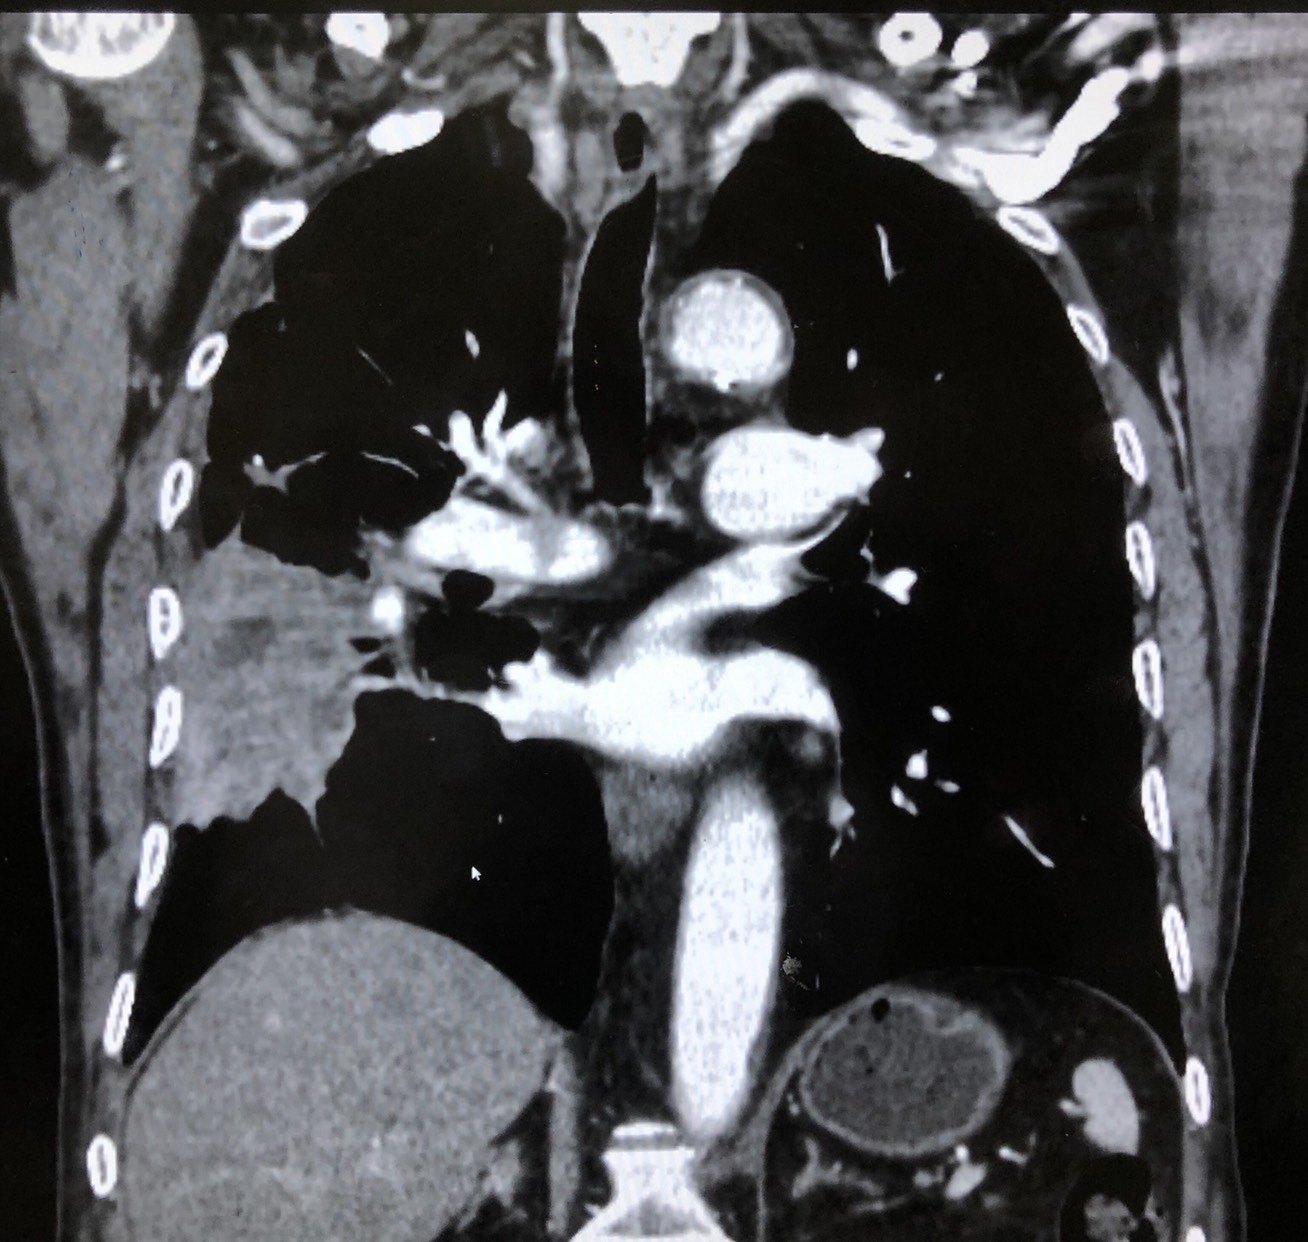

患者男性八十岁,发现右肺肿瘤行氩氦刀冷冻消融治疗同时肺活检,病理提示鳞癌,半月后复查,提示肿瘤基本坏死。七个月后复查,发现肿瘤进展,患者拒绝再次消融或者粒子植入治疗,建议靶向治疗。

图1 右肺占位

图4